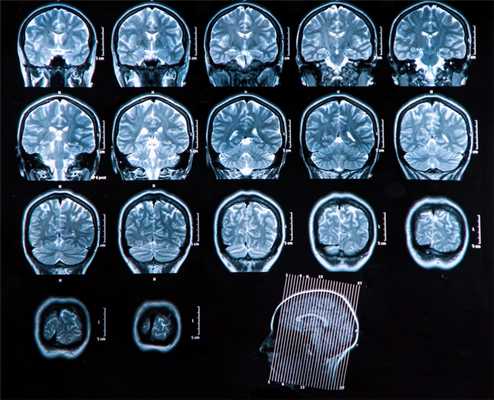

Основной метод оценки непосредственно вещества головного мозга (в том числе первичных опухолей и метастазов) — МРТ с применением контрастного усиления.

Вопросы стадирования (поиск отдаленных метастазов) лучше всего решаются с помощью ПЭТ, в том числе с метионином.

Компьютерная томография используется как дополнительный метод в случае, если требуется оценка состояния костных структур, а также при наличии абсолютных противопоказаний к МРТ исследованию (наличие металла в теле — например, кардиостимулятора, ферромагнитных инородных металлических соединений: пластины, протезы, импланты и т.п.)